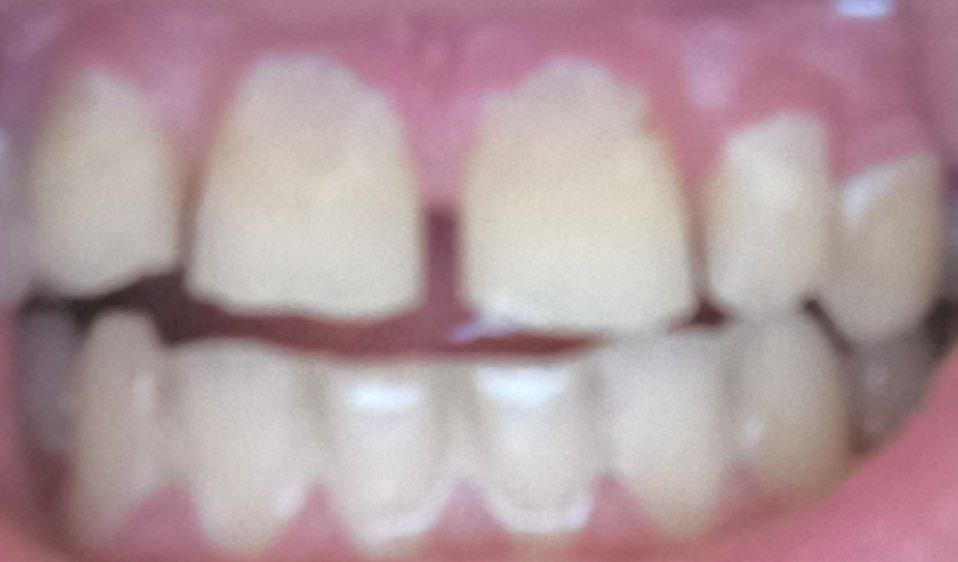

Блять просто начать лечить 3 третью неделю не могу. Ну хотя бы нашёл врача который не говорит, плати а потом посмотрим что будет.

Схема вообщем вскрывают, удаляют нервы, лекарство внутр и хожу с временной пломбой, потом точат временную коронку потом постоянную. На все про все 35-40 тыс подешевле, 45-65 подороже с выебонами

Аноним 29/07/25 Втр 00:02:56 #22 №1633672

Скоро буду ставить брекеты,по крайней мере готовлюсь,на консультациях не был. К чему готовится? Больно ставить брекеты? Не натирает? На сколько строго с пищей? Буду признателен за каждый описанный опыт с брекетами или краткому описанию о жизни с железом во рту

Аноним 29/07/25 Втр 09:59:45 #23 №1633720

>>1633636